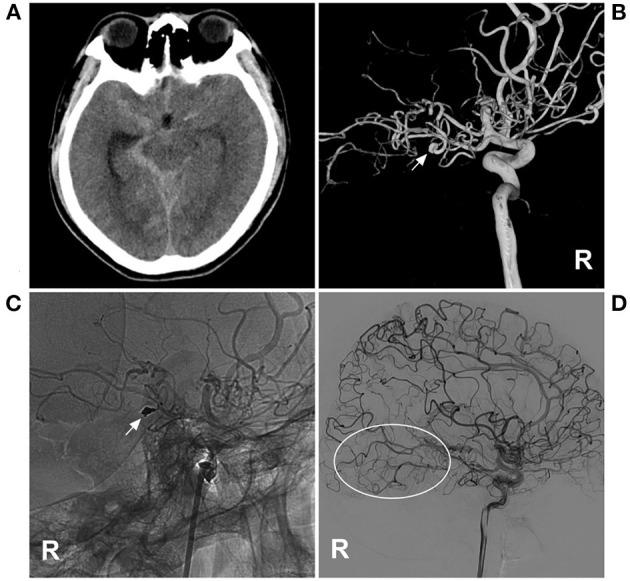

Parent artery occlusion for ruptured aneurysms in moyamoya vessels or on collaterals.

Aneurysms in moyamoya vessels or on collaterals are difficult to treat. Parent artery occlusion (PAO) endovascular treatment (EVT) is often the last resort, but the safety and efficacy of this approach need to be evaluated.

A retrospective study was performed on patients admitted to our hospital who were diagnosed with unilateral or bilateral moyamoya disease (MMD) associated with ruptured aneurysms in moyamoya vessels or on collaterals. These aneurysms were treated with PAO, and the clinical outcome was recorded.

Eleven patients were aged 54.7 ± 10.4 years, and six patients were male (54.5%, 6/11). The aneurysms in 11 patients were single and ruptured, and the average size was 2.7 ± 0.6 mm. Three (27.3%, 3/11) aneurysms were located at the distal anterior choroidal artery, 3 (27.3%, 3/11) were at the distal lenticulostriate artery, 3 (27.3%, 3/11) were at the P2-3 segment of the posterior cerebral artery, 1 (9.1%, 1/11) was at the P4-5 segment of the posterior cerebral artery, and 1 was at the transdural location of the middle meningeal artery. Among the 11 aneurysms, PAO by coiling was performed on 7 (63.6%, 7/11), and Onyx casting was performed on 4 (36.4%, 4/11). Of 11 patients, 2 (18.2%, 2/11) suffered intraoperative hemorrhagic complications. During follow-up, all patients had good outcomes with a modified Rankin scale score of 0-2.

As a last resort, the application of PAO with coiling or casting Onyx for ruptured aneurysms in moyamoya vessels or on collaterals may be safe with an acceptable clinical outcome. However, patients with MMD may not always achieve expected health outcomes, and PAO for the aneurysm can bring only temporary relief.